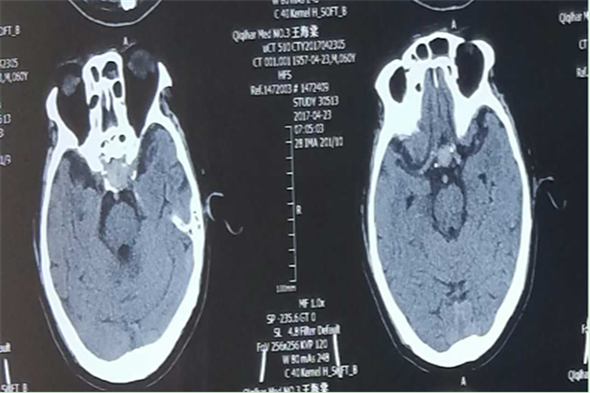

术后1日复查头部CT检查